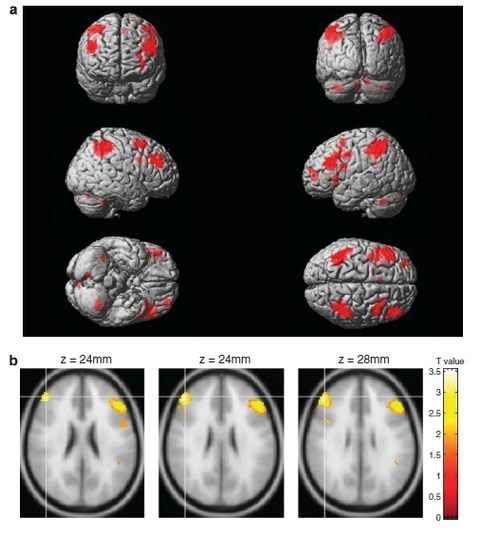

特に深刻なのは加齢による前頭葉、特に、前頭前野(PFC)の機能低下ですね。PFCはいろんな重要な認知機能に関与しております。

(加齢による前頭葉、特に、PFC機能の低下)

メンタライゼーションは他人の精神状態を推測する能力です。言い換えれば、他人の心を思いやることができる能力です。fMRIを使用した研究などでは、高齢者のメンタライゼーション能力が低下していることが既に判明しています。

若者達が私たちの気持ちを理解してほしいと政治家に訴えても、dMPFCという重要な脳の領域の機能が低下しているので、頑張って感染防止に努めながら行動している若者の心情などは、高齢の政治家は理解し思いやることはないでしょう。